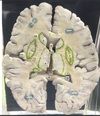

1. Identify the structure labelled 1. 2. Identify the structure labelled 2. 3. Identify the structure labelled 3 4. Identify the structure labelled 4. 5. Identify the specific structure labelled 6.

1. Head of Caudate 2. Globus pallidus of lentiform nucleus 3. Putamen of lentiform Nucleus 4. Thalamus 5. Genu of corpus callosum

65

1. Identify the specific structure labelled 7. 2. Identify the specific structure labelled 8. 3. Identify the specific structure labelled 9. 4. Identify the specific structure labelled 11. 5. Identify the structure labelled 14.

1. Anterior Limb of internal Capsule, frontopontine, thalamocortical 2. Genu of Internal Capsule 3. Posterior limb of Internal capsule, corticospinal 4. Spleenium of corpus callosum 5. Insular cortex

66

1. Identify the structure labelled 5. 2. What is the immediate medial relation of the identified structure? 3. What is the immediate lateral relation of the identified structure?

1. Claustrum thin, irregular, sheet-like neuronal structure hidden beneath the inner surface of the neocortex in the general region of the insula. Its function is enigmatis 2. Putamen 3. Insular Cortex

67

1. Identify the structure labelled 10. 2. Where does this structure commence? 3. Where does this structure end? 4. From the cavity of lateral ventricle, what layers must be traversed in order to access the structure labelled 10?

1. Optic Radiation 2. Lateral Geniculate body 3. Primary visual cortex (calcarine fissure) 4. Ependymal layer, Tapetal layer

68

1. Identify the specific space labelled 12. 2. What is the embryonic origin of this structure? 3. Identify the specific space labelled 13. 4. What is the embryonic origin of this structure?

1. Anterior horn of lateral ventricle 2. Cavity of telencephalic vesicle 3. Posterior horn of lateral ventricle 4. Neural tube